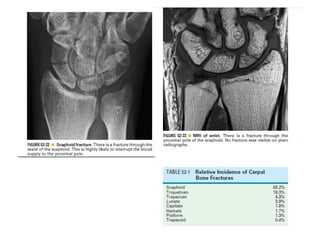

Skeletal trauma was presented by Dr Laith Fadhel with reference to Grainger's Diagnostic Radiology textbook. The presentation covered skeletal trauma as assessed through diagnostic radiology techniques. Key findings and treatments for skeletal injuries were likely discussed.